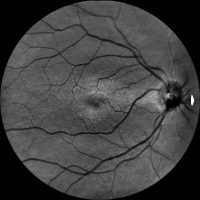

Dzięki technologi SLO – Scanning Laser Ophthalmoscope, podczerwieni oraz wiązki zielonego laseru, jesteśmy wstanie wykonać bardzo dokładny zrzut dna oka, dzięki czemu wykryjemy praktycznie każde zmiany w gałce ocznej. W realizacji takiego skanu nie potrzebne jest zakroplenie oka co znacznie usprawnia nam diagnostykę pod katem szybkości badania czy samopoczucia osoby poddanej tejże czynności. Badanie ma na celu wykrycie zmian w oku jak: jaskra, zaćma, zatory żylne, męty, retinopatie cukrzycową czy AMD(zwyrodnienie plamki żółtej), Pełna wizyta obejmuje: